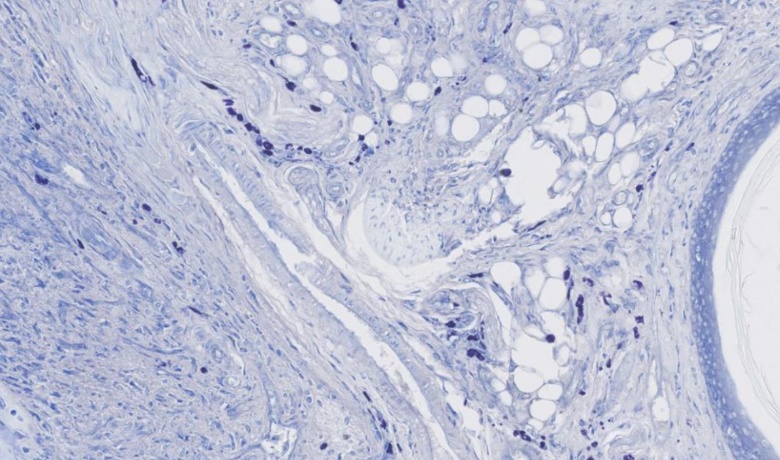

甲苯胺蓝染色

甲苯胺蓝是一种常见的人工合成染料,属于醌亚胺染料类。此类染料具有胺基和醌型苯环两个发色团,因此能够显示出独特的颜色。甲苯胺蓝中的阳离子发挥着染色作用,与组织细胞中的酸性物质结合,从而实现染色效果。甲苯胺蓝不仅含有两个发色团,还含有两个助色团,这些助色团有助于染料产生电离,形成盐类,增强发色团对组织的染色能力。这种染料能够在切片上有效染色细胞核,使其呈现出蓝色的特征。

甲苯胺蓝染色实验是一项常用的生物实验,其目的是利用甲苯胺蓝染料对生物样本进行染色,从而使细胞或组织中的特定结构或成分得以可视化。这一实验方法在生物学研究和临床诊断中具有广泛的应用。 在甲苯胺蓝染色实验中,首先需要将待染色的样本固定并固定在载玻片上。随后,通过一系列处理步骤,如脱水、清洗和脱脂,将样本预处理为适合于染色的状态。接下来,将甲苯胺蓝染料溶液加入样本中,允许染料与样本中的特定成分发生化学反应,从而形成染色物质。 甲苯胺蓝染色实验的最终结果是通过显微镜观察染色样本,并使用适当的滤光片和镜头来增强显像。这样,我们就能够清晰地观察到细胞或组织的特定结构,如细胞核、细胞质和细胞膜,并对其形态和组成进行分析。 甲苯胺蓝染色实验的可视化结果是实验方案的关键部分,因为它们提供了对样本中特定结构或成分的定性和定量信息。此外,由于甲苯胺蓝染料对多种生物样本具有亲和性,因此该实验方法适用于多种生物学研究领域,如细胞生物学、组织学和病理学。 综上所述,甲苯胺蓝染色实验是一种优秀的生物实验方法,通过染色样本提供了关于细胞和组织结构的有价值的信息。它为生物学研究和临床诊断提供了有力的工具,促进了我们对生命活动的深入理解。